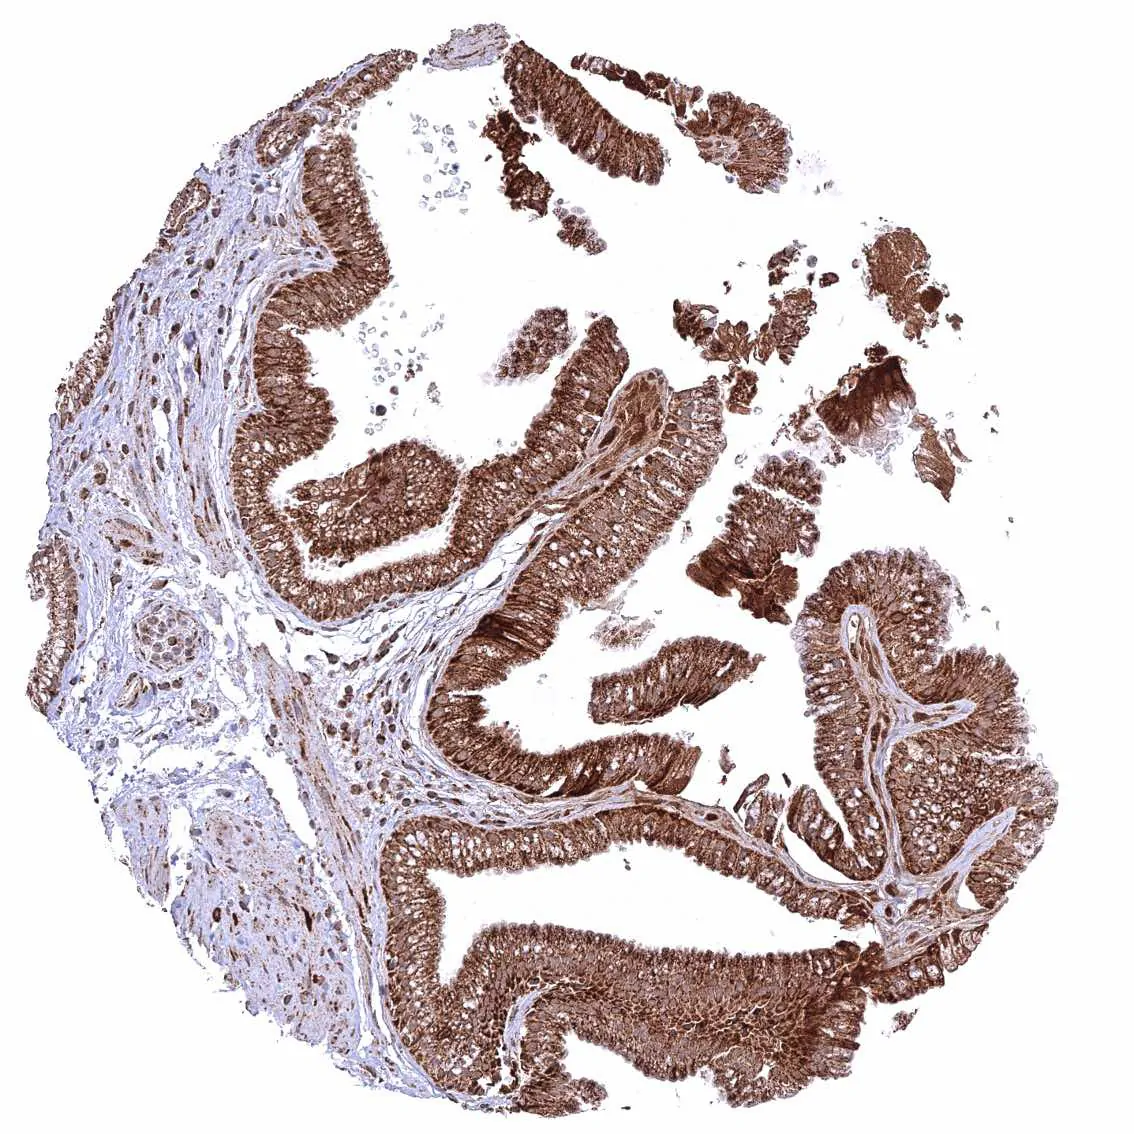

Uterus, endocervix